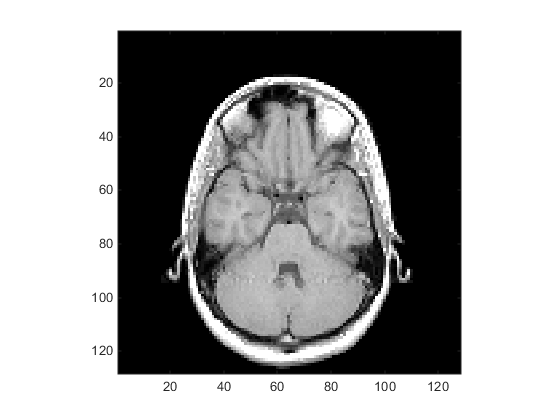

Displaying Images of MRI Data

To display one of the MRI images, use the image command:

figure colormap(map) image_num = 8; image(D(:,:,image_num)) axis image

Save the x- and y-axis limits for use in the next part of the example:

x = xlim; y = ylim;